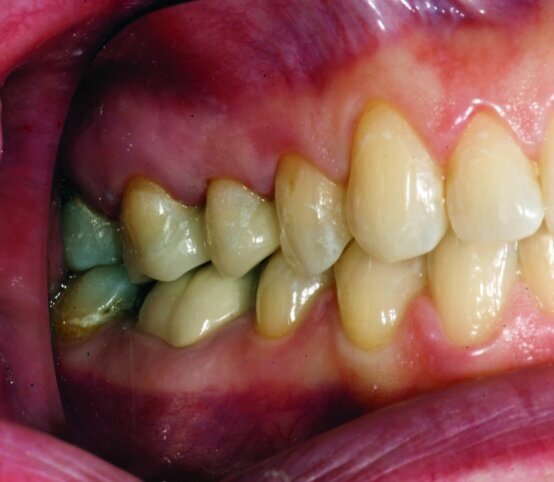

After gross occlusal reduction was completed, the remaining enamel ring was measured (Figs. 9a, b). The enamel rings were noted to be 1.5 mm, and the teeth were prepared for adhesively retained restorations. If the enamel rings were less than 1 mm, the teeth would have been prepared on the axial walls to create retention for cohesively retained crowns.

The remainder of the existing composite resin in #3 and the amalgam in #4 were removed. The occlusal surfaces of the preparations were blended into the interproximal areas using a KS2 bur to create smooth preparations (Figs. 10–15c). There was no retention or resistance form prepared to retain the restorations.